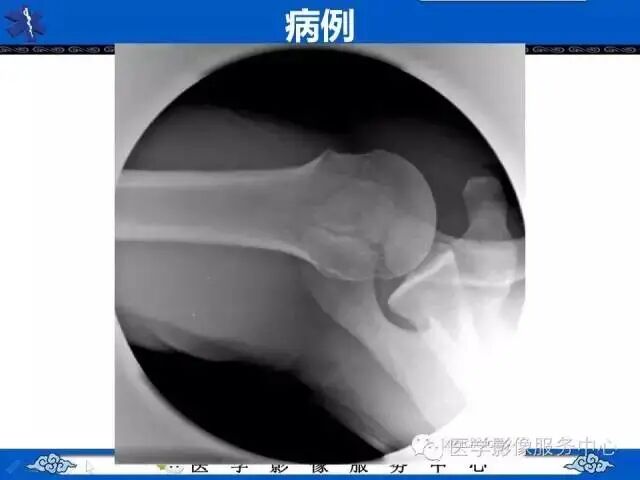

上述病例所示,肩峰处骨皮质不连续、骨小梁中断。如果是外伤患者,按照常规思考,相信有很多同行朋友们会考虑骨折。

我们为大家讲解的知识点为肩峰骨骺,希望大家在临床工作中遇到类似影像图像,能够正确诊断。

不融合的最常见部位是后肩峰与中肩峰之间处(下图箭头处)。